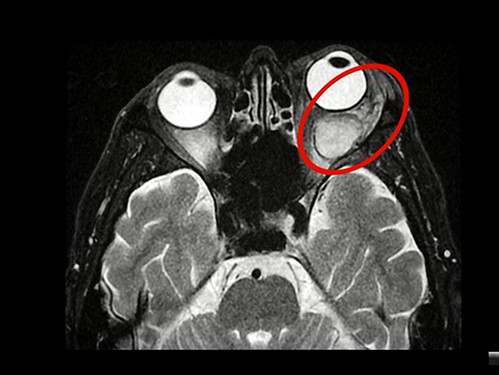

「你凸眼加上視力衰弱,這很嚴重,要趕快去花蓮慈院就診。」經臺東某醫院的轉介,林先生來到花蓮慈院眼科李原傑主任的門診就診,經電腦斷層檢查確認是眼窩異常,轉由眼瞼眼窩整型專長的陳南詩醫師收治。陳南詩醫師用「驚心動魄」來形容她第一次看到電腦斷層報告的心情,「這麼大的腫瘤就在眼睛旁邊,而且,已經擠壓視神經。」陳南詩醫師說,林先生罹患的是「不得了」的腫瘤,需要立刻處理。

圖:林先生飽受左眼突出之苦三十多年,右為電腦斷層檢查,圈起處即為造成眼凸的眼窩腫瘤。